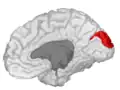

![]() Medial surface of left cerebral hemisphere. (Cuneus visible at left in red.) | |

The cuneus (from Latin 'wedge'; pl.: cunei) is a smaller lobe in the occipital lobe of the brain. The cuneus is bounded anteriorly by the parieto-occipital sulcus and inferiorly by the calcarine sulcus.

Position of cuneus(red) of left cerebral hemisphere. -

Medial surface of left cerebral hemisphere. Cuneus is visible at left in green. -